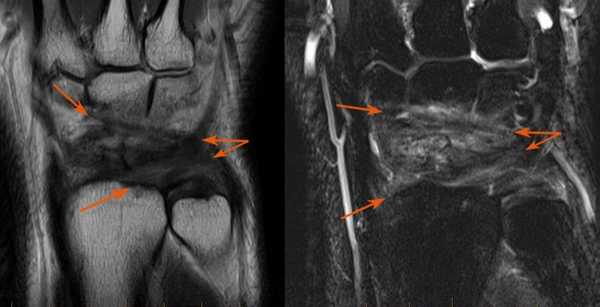

(Слева) МР-артрография в режиме Т1ВИ, коронарный срез: визуализируется очень крупный дефект центральной части ТФХК. Отмечаются дегенеративные изменения периферической части ТФХК. Следует отметить патологическое расширение суставной щели ДЛЛС.

(Справа) Непрямая МР-артрография в режиме Т1ВИ FS, коронарный срез: определяются подострый перелом шиловидного отростка локтевой кости, разрыв периферических мест прикрепления ТФХК и патологическое скопление жидкости в ДЛЛС. В норме в полости ДЛЛС жидкость не визуализируется. (Слева) МР-артрография в режиме Т1ВИ FS, коронарный срез: визуализируется распространение контрастного препарата в ДЛЛС и вокруг влагалища сухожилия ЛРЗ через периферическую часть ТФХК, расположенную возле шиловидного отростка локтевой кости.

(Справа) МР-артрография в режиме Т1ВИ FS, коронарный срез: определяются разрывы периферических мест прикрепления ТФХК. Жидкость, введенная в лучезапястный сустав, поступает в ДЛЛС. (Слева) КТ-артрография, коронарный срез: визуализируется интактный ТФХД. Однако свободное распространение контрастного препарата за пределы лучезапястного сустава через локтевую часть суставной капсулы свидетельствует о наличии периферического разрыва.

(Справа) МР-артрография в режиме Т1ВИ FS, коронарный срез: отмечается отрыв ТФХК от шиловидного отростка. При этом ТФХК остается прикрепленным к ямке, а контрастный препарат в ДЛЛС не поступает.